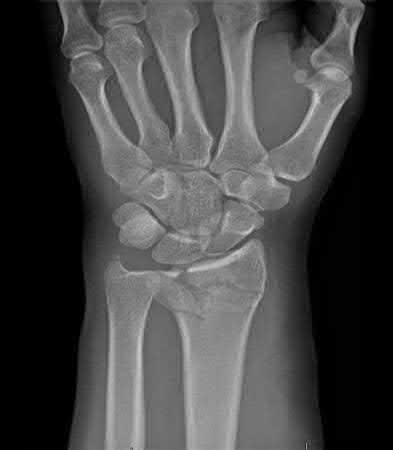

A 25-year-old male sustains an ankle fracture dislocation and undergoes open reduction and internal fixation. He returns to clinic five months following surgery complaining of continued ankle pain and instability with weight bearing. His immediate post-operative AP radiograph is seen in Figure A. Which of the following could have prevented this patient from developing persistent pain?

The patient presents with continued ankle pain and instability following open reduction and internal fixation. The radiograph in figure A demonstrates inadequate restoration of fibular length, likely leading to continued tibiotalar instability.

Illustration A demonstrates fibular malreduction with dislocation of the fibula anterior to the tibial incisura. Illustration B shows a comminuted fibula fracture along with a measurement of length from an intact fibula. The arc from the lateral process of the talus to the peroneal groove of the distal fibula is known as the "dime" sign and should remain unbroken if fibular length has been restored. Illustration C demonstrates the use of a push-pull screw and lamina spreader to regain length intraoperatively for a comminuted fibula fracture.

Chu and Weiner review management of malunions of the distal fibula. The authors state that restoration of fibular length, alignment and rotation leads to reduction of the talus, provides a buttress to talar motion in the setting of an incompetent deltoid, and allows the syndesmotic ligaments to heal at the appropriate tension.

Wikeroy et al conducted a study of patients from a prior prospective, randomized control trial comparing different methods of syndesmotic fixation. There was no significant difference in outcomes between tricortical or quadricortical 3.5mm screw fixation, however worse outcomes were seen with associated posterior malleolar fractures, obesity, a difference in sydesmotic width of 1.5mm or greater, and a CT confirmed tibio-fibular synostosis.

Sinha et al present a simple technique for fibular lengthening in the setting of distal fibula malunion. They found high union rates and improved AOFAS scores at short-term follow up with their technique.